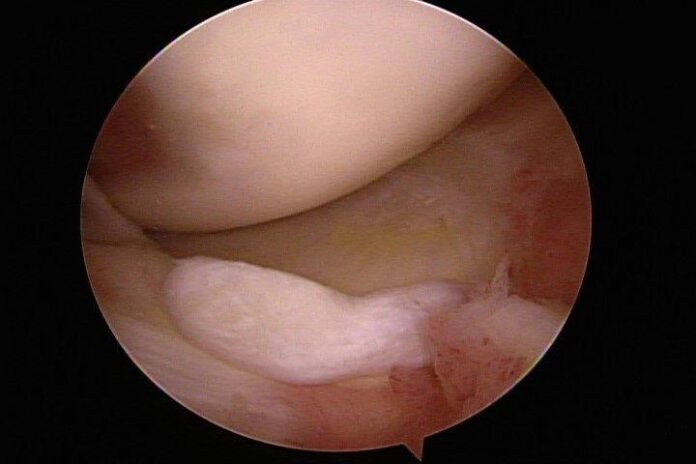

臺北市立聯合醫院忠孝院區骨科主治醫師林心畬表示,輕微的磨損注射玻尿酸潤滑即可緩解,但較嚴重的損傷會導致軟骨破裂,有時軟骨會移位,碎片會脫落,形成大問題。關節軟骨出現較大破損時,會有明顯的凹凸不平甚至會剝落形成碎片,活動時容易卡住,也會有突發的無力感,還會發炎腫脹產生關節內積水。休息跟吃消炎藥可暫時緩解,但症狀時常反覆,造成一大困擾,這時就會需要手術介入。

傳統手術需要切開整個關節來移除碎片或修補軟骨,傷口大,復原慢,有時還會遇到手術後沾黏僵硬的後遺症。但是現在內視鏡技術已經普及化,搭配關節專用的內視鏡器械,只需要三個小於一公分的傷口便可完成手術,手術後隔天傷口只會些微腫脹,通常一天內可以恢復獨立下床與走路,住院時間只需兩天一夜。

除了修補軟骨及移除碎片,手術中還可以詳細檢查關節內的狀況,若是發現不平整的皺壁或是發炎的滑膜組織也可同時清除,回復關節的順暢度,延長關節的使用年限。